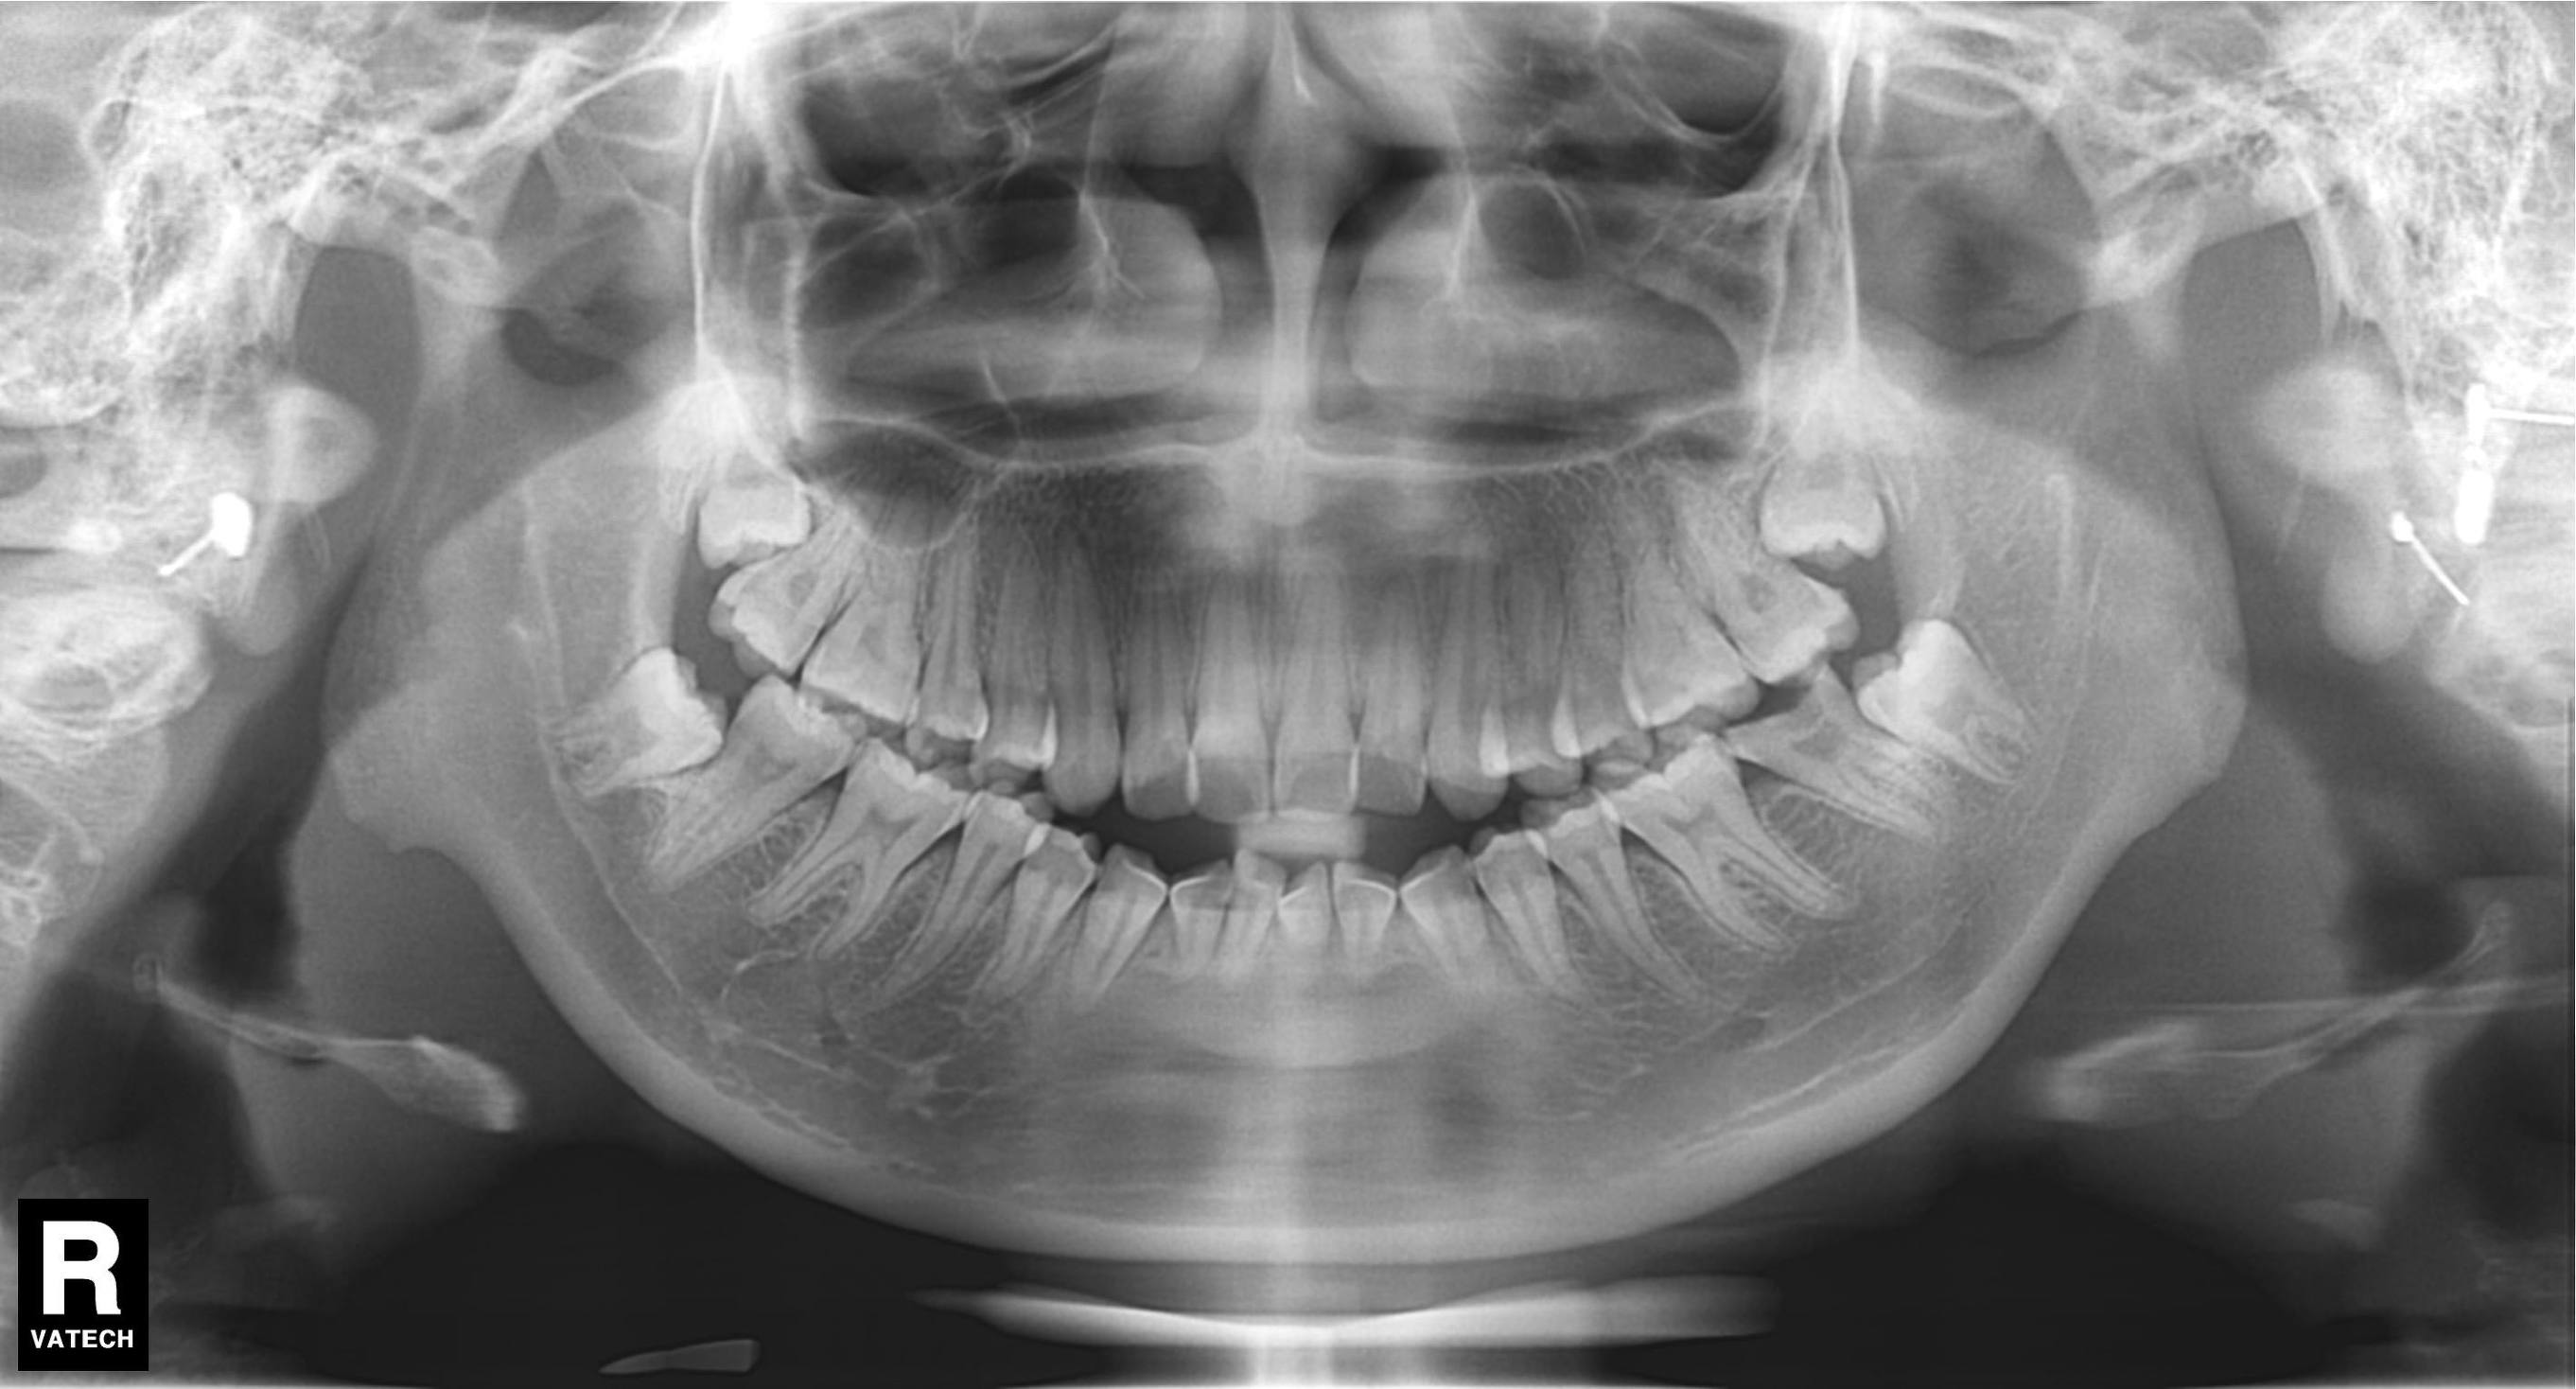

所以,当你去拍片后发现智齿是这样斜靠着的。

或者是这种躺在牙槽骨内的。

还是这种不要脸的,沉睡在牙槽骨里的。